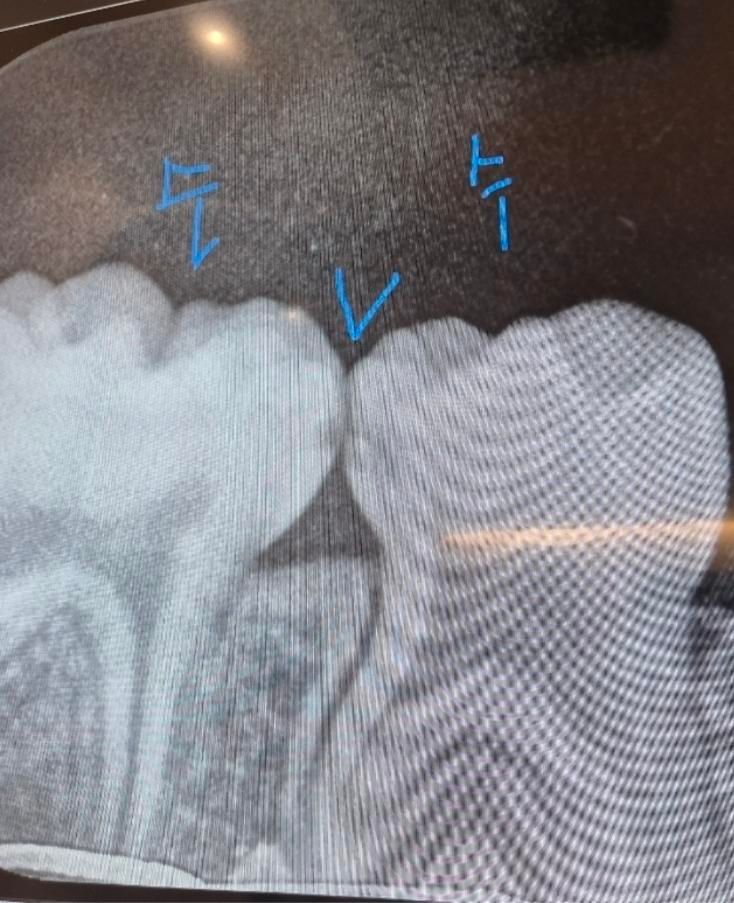

헌재 40개월 만3세 아이입니다 치과에 갔다왔더니 충치가 있다고 레진으로 때워야한다고 하더라과요 3개월정도 지켜보면 어떻냐고 하니까 이건 꼭 충치치료해야한다 안하면 신경치료까지 간다고 하는데, 꼭 해야하는게 맞을까요? 만약 해야한다고 한다면 사진상 빨간색원 왼쪽오른쪽 2개를 다 해야하는건지, 아니면 오른쪽만 하고 왼쪽은 지켜보는게 나을지 어떻게 하는게 좋을까요?

• 2번 째 사진

4. 만3세의 D,E 유치는 제1,2 소구치(영구치)로 대체되기 까지는 아직 시간이 매우 많이 남았습니다. 그래서 충치가 있는 상태에서 불안하게 유지를 하기 보다는 2개 다 치료를 해주는 것이 바람직합니다.

5. 또한 방사선 사진상 보이는 옆면 충치는 비교적 빠르게 충치가 진행되기도 하고, 그쪽으로 계속 음식물이 껴서 관리가 더 어렵기도 합니다.

6. 방사선 사진상에서 보이는 충치보다 실제로 충치는 더 크게 진행되었을 수도 있습니다.

아이들은 충치가 상당히 빨리 진행됩니다. 치아 둘다 사이에 충치가 잇는거 같습니다. 더 진행되기 전에 레진으로 치료를 하시는게 좋을것같습니다.

방사선사진에서는 인접면에 충치가 있는것으로 보입니다. 아이들의 경우 충치가 쉽게 커질수 있기 때문에 예방적으로 치료를 하는경우가 많습니다.